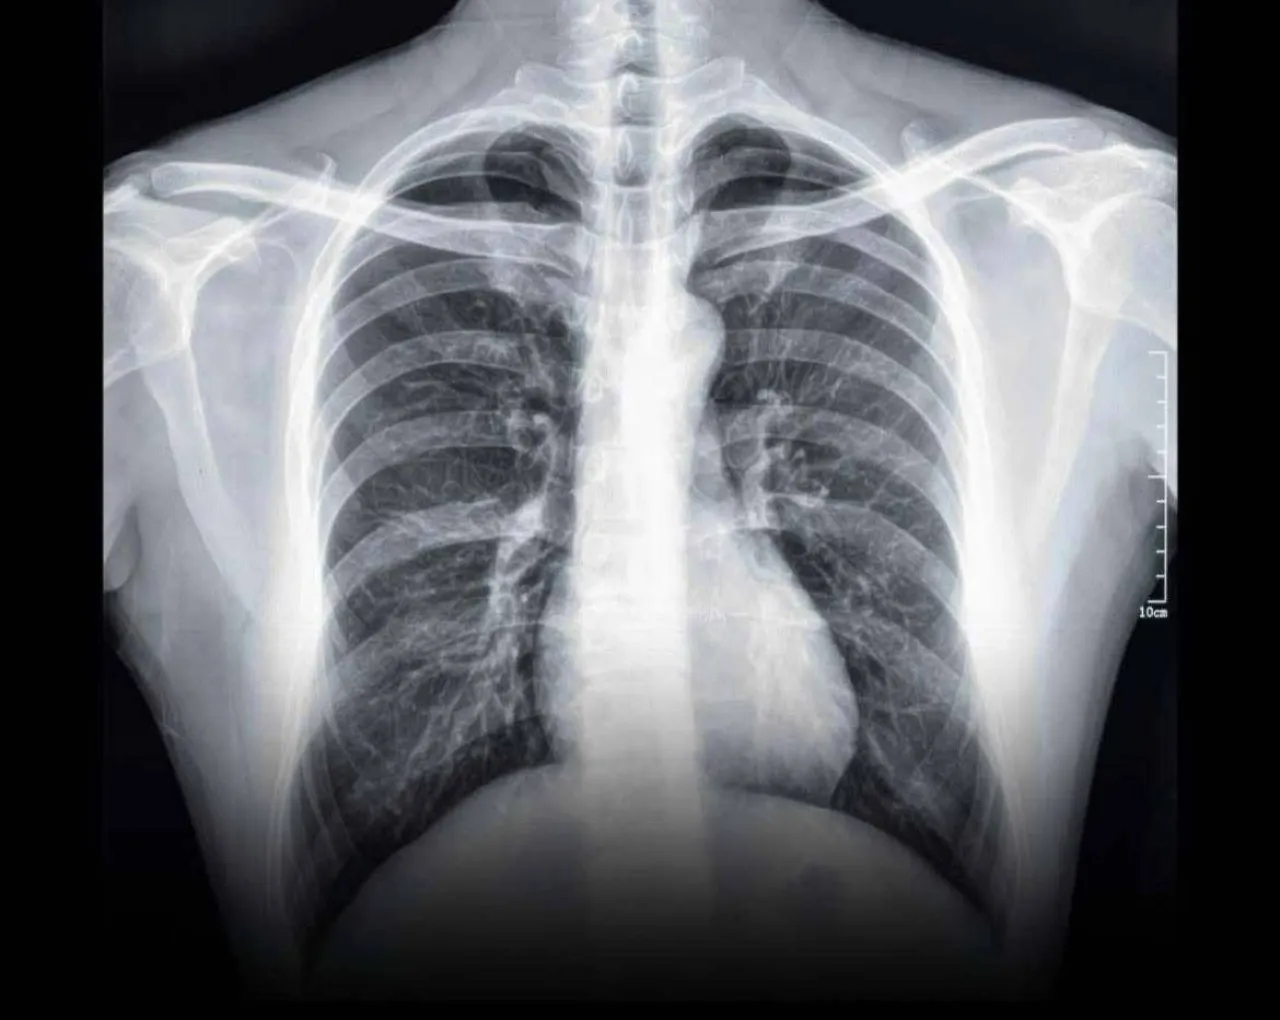

ونشرت قاقيش صورة شعاعية لرئة مراهق يبلغ من العمر 16 عاماً، أصيب بتليف رئوي حاد بعد عام فقط من استخدامه لجهاز “الفيب” بشكل سري بعيداً عن علم أهله، ما استدعى إدخاله في حالة صحية حرجة استلزمت الاعتماد الكامل على الأوكسجين، مع منعه من ممارسة أي نشاط رياضي.

وأشارت الدكتورة إلى أن هذه الحالة مصابة بما يُعرف بـ “Popcorn Lung” أو “Bronchiolitis Obliterans”، وهي حالة خطيرة تسببها مواد كيماوية تُستخدم في سوائل الفيب، مثل “Diacetyl” و”Acetoin”، رغم محاولة بعض الشركات خداع المستهلكين بإزالة اسم المادة الأولى فقط من عبواتها.